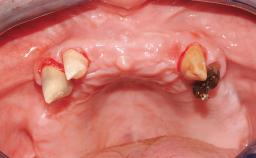

Immediate Loading of Eight Implants in the Maxilla and Six Implants in the Mandible and Final Restoration with Three-Unit and Four-Unit FDPs

Case Type Edentulous Maxilla

Defining Characteristics Fully edentulous upper jaw to be rehabilitated with four or more implants